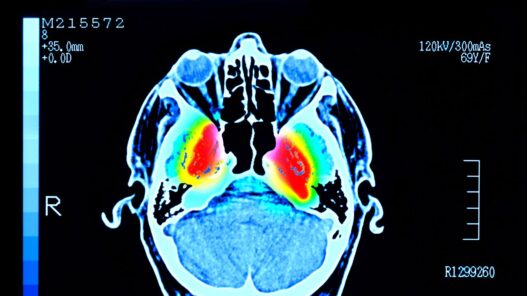

La enfermedad de Parkinson es una afección cerebral que empeora con el tiempo. Tiene su origen en la pérdida de neuronas productoras de dopamina, lo que altera la comunicación en los circuitos del cerebro que controlan el movimiento. El síntoma más conocido son los temblores involuntarios, pero también hay rigidez, lentitud de movimientos y problemas de equilibrio, además de manifestaciones no motoras como alteraciones del sueño, depresión o deterioro cognitivo.

Aunque el Parkinson no tiene cura, un mejor entendimiento de las causas que detonan la pérdida de neuronas dopaminérgicas podría desembocar en mejores tratamientos preventivos. Sin embargo, tampoco está claro qué desencadena ese deterioro, ni por qué ciertas neuronas (como las de una región del cerebro llamada sustancia negra, SNc) se ven más afectadas que otras (como las de la región del área tegmental ventral, VTA).

Aunque las neuronas en cuerpos celulares todavía estaban mayormente intactas en ese periodo (tanto en la SNc como en la VTA), la pérdida de axones ya era notable desde la primera semana. Una vez transcurrido el mes (cuatro semanas), comenzó a observarse muerte neuronal en los cuerpos celulares. Las neuronas de la SNc fueron mucho más vulnerables al daño que las de la VTA. Además, las fibras que conectan la SNc con el estriado dorsal fueron las primeras y más gravemente afectadas.